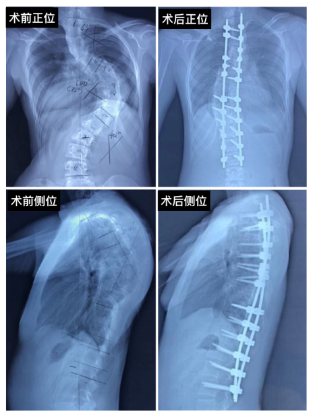

在第二关中,你是在全身麻醉状态下渡过的。由手术医生、麻醉医生、手术室护士组成的大约十人的团队来帮助你把脊柱变直。下面的X线片子是手术前和手术后脊椎正侧位的对比(图1)。骨科医生会在你的脊柱两侧置入多对金属钉,然后把两根矫形棒固定在钉子上,这样你的脊柱就会像右侧的X线片一样变直了,说起来简单,但这可需要经验丰富的手术医生施展高超的技艺才能完成!

图1.脊柱侧弯患儿脊柱正侧位X线检查术前术后对比